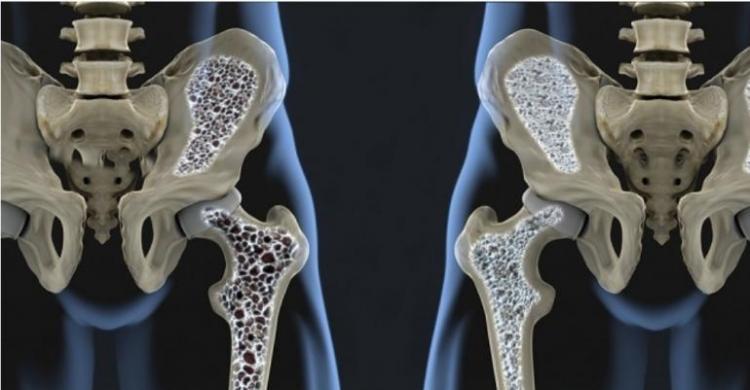

"Akibatnya, tulang kita menjadi keropos atau yang biasa disebut dengan osteoporosis. Selain itu, mager juga bikin otot kita menjadi lemah," kata Ahli Penyakit Dalam RSUD Dr. Soetomo Surabaya, dr. Decsa Hertanto, Sp. PD melalui akun Instagramnya.

"Selama ini, kita tahu osteoporosis dialami oleh kelompok lansia. Namun, karena mager sudah menjadi budaya, maka terjadi pergeseran penyakit osteoporosis ke populasi yang lebih muda. Ini tentu menyedihkan," sambungnya sebagaimana dilansir dari RM.id.